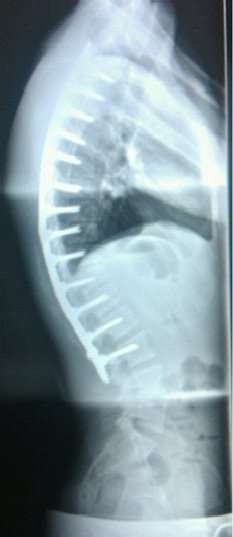

Scheuermann's disease can be successfully corrected with surgical procedures, almost all of which include spinal fusion and hardware instrumentation, i.e., rods, pedicle screws, etc. While many patients are typically interested in getting surgery for their correction, it is important to realize the surgery aims to reduce pain, and not cosmetic defect. As always, surgical intervention should be used as a last resort once conservative treatment fails or the patient's health is in imminent danger as any surgical procedure is not without risk; however, the chances of complication are relatively low and the surgeries are often successful.

One of the largest debates surrounding Scheuermann's disease correction is the use of very different correction procedures. There are different techniques to correct kyphosis; usually the differences being posterior/anterior entry or posterior entry (rear) only. The classic surgical procedure partially entails entering two titanium rods, each roughly one and a half feet long (depending on the size of the khyphosis), into the back on either side of the spine. Eight titanium screws and hardware are drilled through the bone and secure the rods onto either side of the spine. On the internal-facing side of the spine, ligaments (which can be too short, pulling the spine into the general shape of kyphosis) must be surgically cut or released, not only stopping part of the cause of the kyphosis, but also allowing the titanium rods to pull the spine into a more natural position. Normally, the damaged discs between the troubled vertebrae (wedged vertebrae) are removed and replaced with bone grafting from the hip or other parts of the vertebrae, which once healed or 'fused' will solidify. The titanium instrumentation holds everything in place during healing and is not necessary once fusion completes. Recovery begins in the hospital and depending on whether the operation is one- or two-stage the patient can expect to be in hospital for minimum of a week, possibly longer depending on recovery. They will then often be required to wear a brace for several months to ensure the spine heals correctly leaving the patient with the correct posture. The titanium instrumentation can stay in the body permanently, or be removed years later. Patients undergoing surgery for Scheuermann's disease often need physical therapy to manage pain and mobility, however their range of motion is generally not limited very much. Recovery from kyphosis correction surgery can be very long; typically patients are not allowed to lift anything above 5 or 10 pounds for 6 months to a year. Many are out of work for at least 6 months. However, once the fusion is solidified, most patients can return to their usual lifestyle within one to two years.